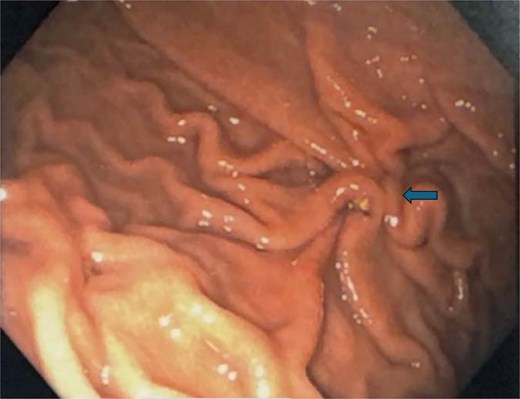

Postoperatively, the patient was admitted and received broad-spectrum antibiotics. An upper gastrointestinal series on postoperative day (POD) 1 demonstrated no leakage from the repair. The nasogastric tube was removed, and her diet was advanced from clear liquids to a regular diet by POD3. The peritoneal drain was removed on POD3, and the patient was discharged home. Final biopsy pathology revealed chronic inactive gastritis and tested negative for Helicobacter pylori. A follow-up endoscopy 3 months later showed a well-healed closure site (Fig. 5).

Follow-up endoscopy 3 months postoperatively demonstrating a well-healed suture line.